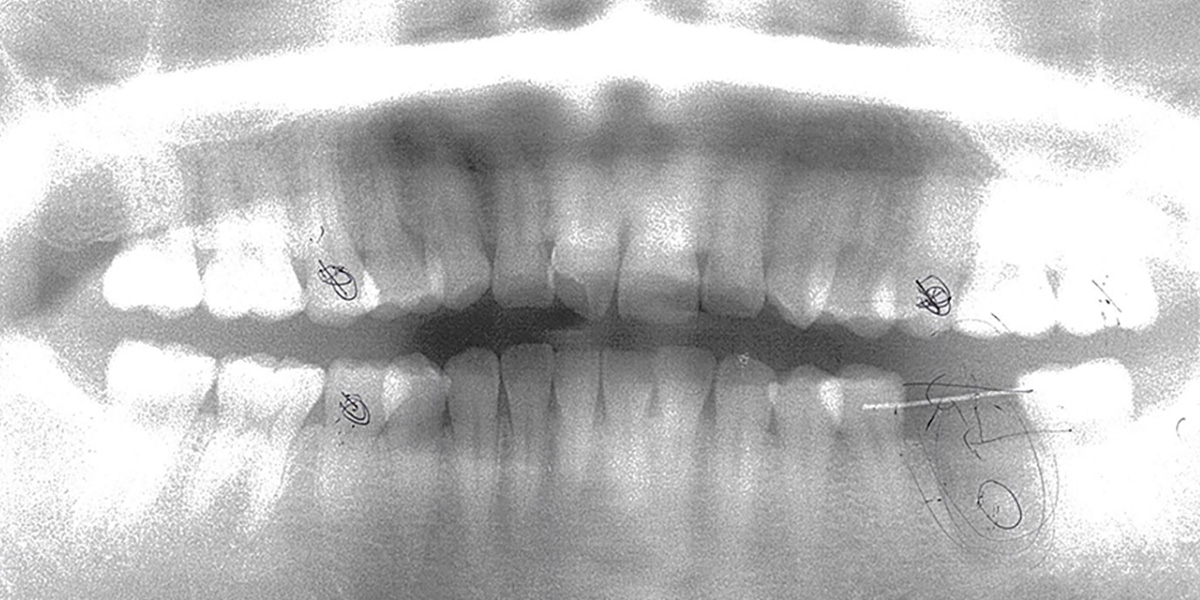

■ レントゲン(治療前)

■ レントゲン(治療後)